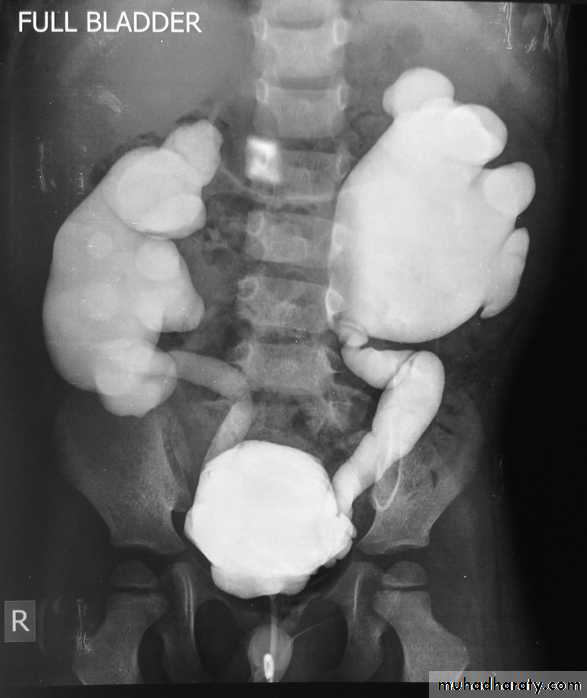

Micturating Cystourethrography (MCUG)

VUR is classified into 5 grades depending on the severity of reflux and the associated dilatation of the renal system.